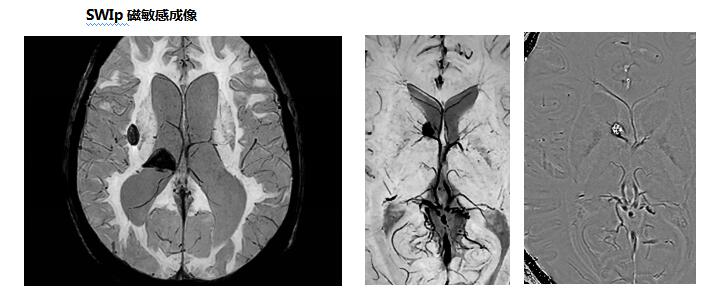

中枢神经系统应用

可应用于颅内外肿瘤性病变,脑卒中病变、血管性病变、感染性病变、外伤性病变,脑白质病变,先天性发育异常、退行性病变等中枢神经系统疾病检查,尤其是脊柱及脊髓病变,同时可以全脊柱成像,整个脊柱及脊髓病变一览无余,无处藏身。